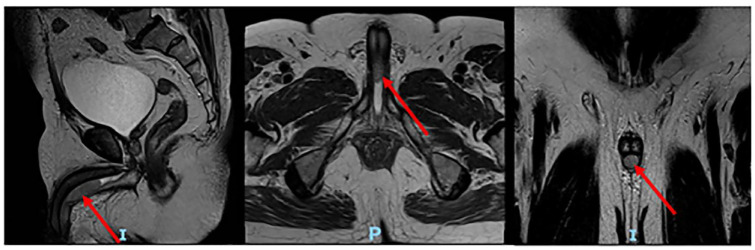

Results: The patient was diagnosed with recurrent bladder cancer in the urethral after radical cystectomy using magnetic resonance imaging of the pelvis, cystoscopy, and biopsy. Complete urethrectomy and creation of a permanent percutaneous urinary diversion were performed. No intraoperative or postoperative complications were recorded. The patient was discharged 3 days after the surgery.

Abstract Image